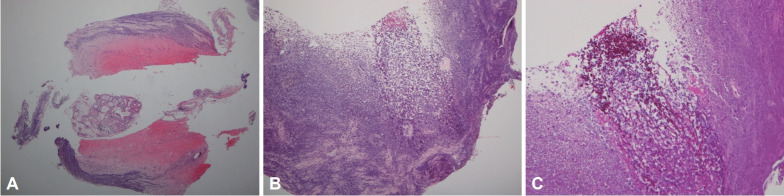

急性食管坏死(AEN),也被称为“黑色食管”,是一种罕见的临床疾病,其特征是食管内壁组织严重损伤和死亡。在内窥镜检查时,AEN通常呈现黑色外观。AEN的危险因素包括多器官功能障碍背景下的食管缺血、脓毒症、灌注不足、血管病变、创伤性胸主动脉横断、血栓栓塞现象、胃扭转、糖尿病酮症酸中毒、酒精中毒或恶性肿瘤。在此,我们报告一例以呼吸困难和糖尿病酮症酸中毒为表现的AEN病例,该患者以前未被诊断为糖尿病。

Acute esophageal necrosis (AEN), also known as "black esophagus," is a rare clinical condition marked by severe damage and death of the tissue lining the esophagus. During endoscopy, AEN typically presents with a blackened appearance. Risk factors for AEN include esophageal ischemia in the setting of multi-organ dysfunction, sepsis, hypoperfusion, vasculopathy, traumatic transection of the thoracic aorta, thromboembolic phenomena, gastric volvulus, diabetic ketoacidosis, alcohol intoxication, or malignancy. Here, we report a case of AEN diagnosed in a patient presenting with dyspnea and diabetic ketoacidosis who had not been diagnosed with diabetes mellitus previously.